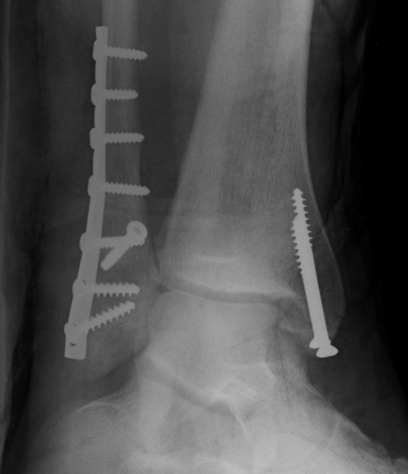

Lateral talar shift / increased medial clear space / deltoid ligament injury

Tibia / fibular overlap < 1mm / syndesmotic injury